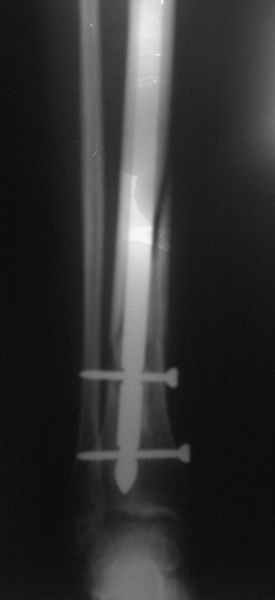

Здравствуйте. 2 апреля я сломала б/берцовую кость. 12 сделали зимо со статическим блокированием, но поставили не те спицы котые мы купили.

Поставили наши, а мы брали импортные.Обещали что пойду через месяц, но прошло уже 3 месяца, а у меня не идет сращение кости. Не могли бы вы сказать почему? еще мне во время операции задели нерв, который идет к большому пальцу, из-за этого он не работает.Я ходила на электрофорез с прозерином не помогло. Электоростимуляця не пошла-очень больно. Скажите пожалуйста возможно ли ускорить сращение и как то восстанивить нерв? спасибо

Верятно, то, что использовали другой стержень, было обусловлено тем, что во время операции купленный не подошел по размеру. Но сделано все неплохо и с этим стержнем.

Если гвоздь был заперт статически, также уже пора его отпереть, убрав один винт вверху - это сделано?

Если сращение не наступит через 2-3 мес. после динамизации гвоздя и ходьбы с полной нагрузкой (это крайне редко, но бывает), оптимально будет заменить стержень на другой, большего диаметра. Как правило, это решает проблему.